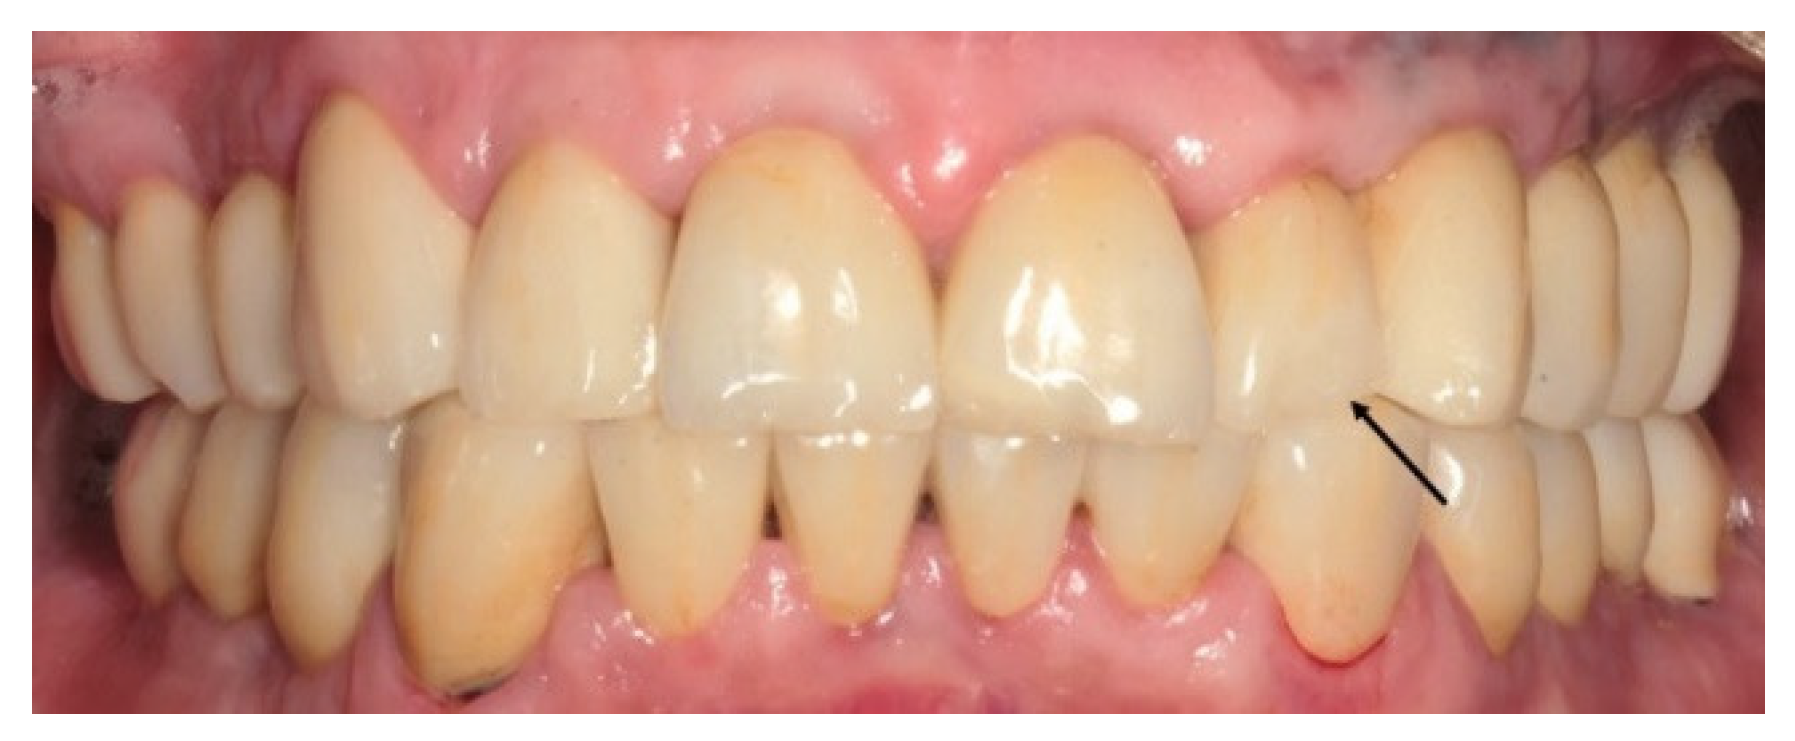

2.4. Methods

2.5. Clinical and Radiographic Assessments and Classification of Observed Events at the Recall Appointment

3.3. Relative Failure and Success of the Treatments

3.4. California Dental Association Ratings